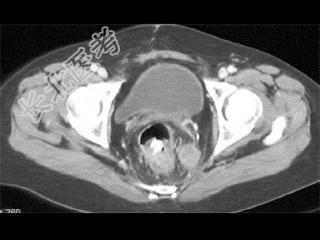

- 单项选择题患者腹痛,便血, 有卵巢癌病史,结合图像, 最可能的诊断是 ( )

A、原发性结肠癌

B、卵巢癌种植转移

C、子宫内膜异位

D、髓外造血

E、以上都不是